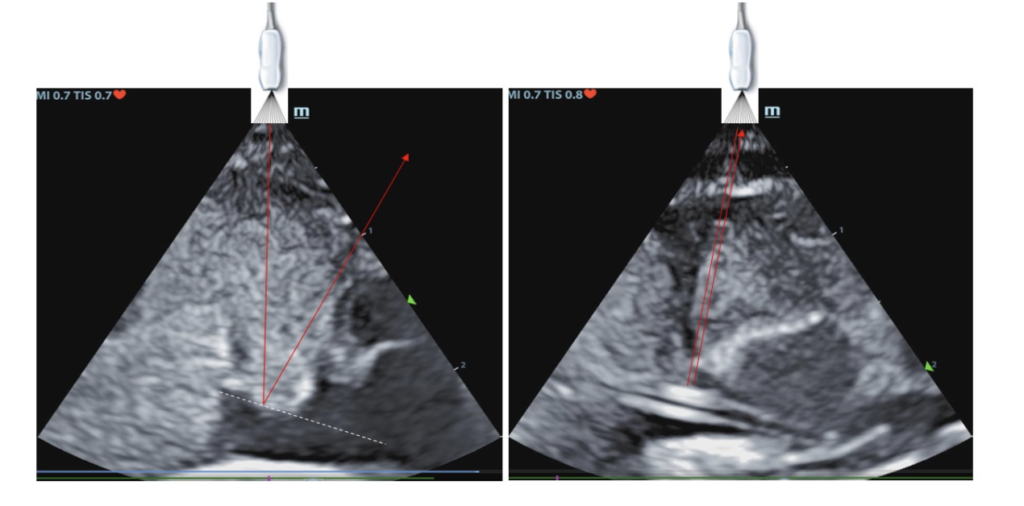

Even if you transect the path through the ductus vensosus to the cava-atrial junction you still may not see the line on USS through the liver parenchyma, you may just be missing the reflection back of the ultrasound beams. Below is the same line, not seen and seen.